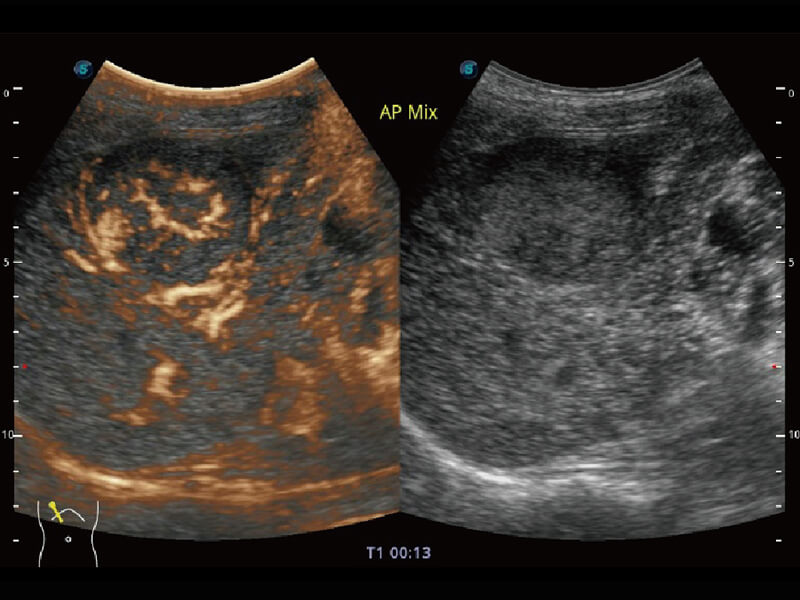

S60探头工艺,从前端信号处理每一个环节采集无损声学数据,真实还原组织原貌,再现解剖细节。